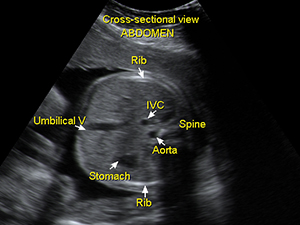

Abdomen